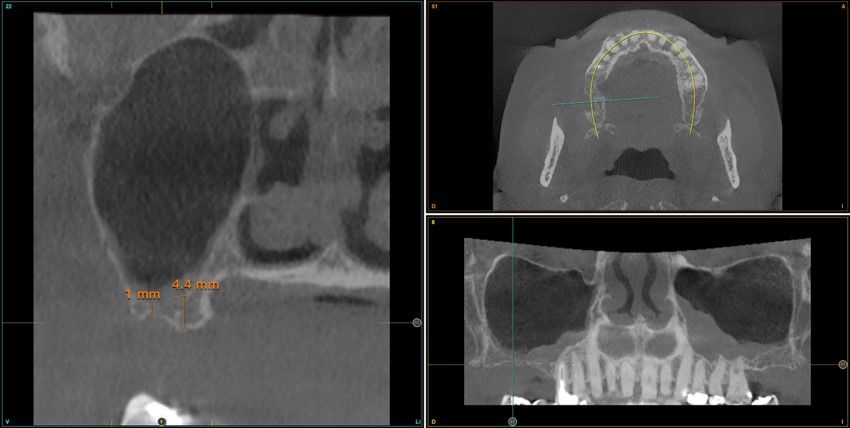

Resultados. Fueron reclutados 13 pacientes en los que se insertaron 30 implantes. Una vez insertados y cargados los implantes, la altura media final fue de 9,68 mm (+/- 2,66), lo que supone una ganancia promedio de 5 mm. A los 10 años, se observó una disminución media de la altura ósea ganada en los implantes en conjunto de 0, 29 mm (+/- 0,77). La media de la pérdida ósea mesial fue de 0,73 mm (+/- 0,75 mm) y la media de la pérdida ósea distal fue de 0,98 mm (+/- 1,2 mm). La supervivencia fue del 100%.

Results.Thirteen patients were recruited and 30 implants were inserted. Once the implants were inserted and loaded, the mean final height was 9.68 mm (+/- 2.66), which represents an average gain of 5 mm. At 10 years, there was a mean decrease in the overall bone height gain of the implants of 0.29 mm (+/- 0.77). The mean mesial bone loss was 0.73 mm (+/- 0.75 mm) and the mean distal bone loss was 0.98 mm (+/- 1.2 mm). Survival was 100%.

Los senos tratados con la técnica de elevación transcrestal sin material de relleno muestran un incremento de entre 2,5 mm12,13 hasta 4.4 mm14,15 en la altura ósea lograda sobre el ápice y una supervivencia de los implantes que se sitúa entre un 94 y un 100%16-17. En este trabajo se presenta un estudio retrospectivo donde se ha evaluado la inserción de implantes extracortos (5,5 y 6,5 mm) en zonas posteriores maxilares mediante la técnica de elevación de seno transcrestal con la fresa de ataque frontal sin la utilización de material de injerto, con un tiempo de seguimiento de 10 años para poder objetivar el comportamiento de los implantes a largo plazo y de la técnica empleada.